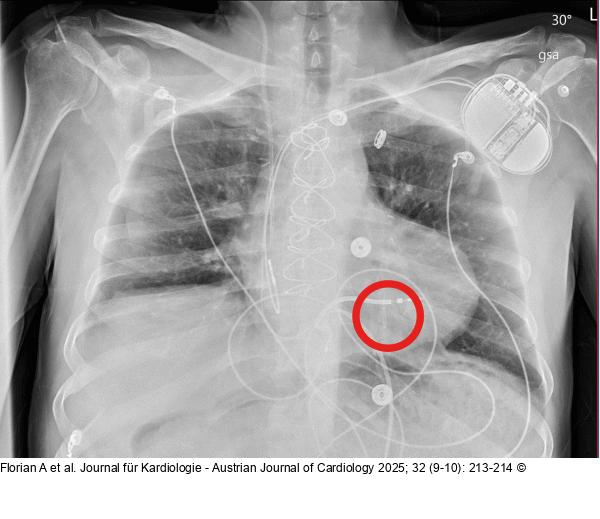

Abbildung 1: Röntgen Präoperatives Röntgen mit implantiertem CardioMEMS-System (roter Kreis) |

Präoperatives Röntgen mit implantiertem CardioMEMS-System (roter Kreis) |